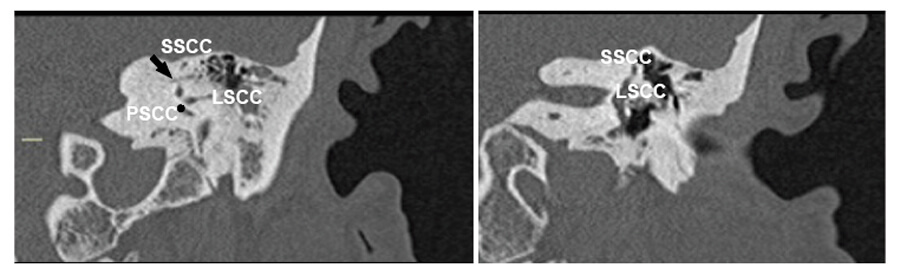

Figure 4. Preoperative temporal bone CT scan on coronal plane of one of the patients treated with triple SCC occlusion (left ear) showing a more sclerotic mastoid with thicker than usual otic capsule at the level of SCC; preoperative imaging is crucial. The arrow shows the subarcuate artery (SSCC: superior SCC; LSCC: lateral SCC; PSCC: posterior SCC* at the level of crus communis).

It is worth mentioning that while in superior SCC dehiscence, the temporal bone is well pneumatised allowing fast access to the canal [5], the anatomy in patients with Meniere’s disease can be variable. On these grounds, preoperative imaging (computed or cone beam tomography) is essential to assess the anatomy (Figure 4). Additionally, a frank discussion with the patient, highlighting not only the expected benefits and risks but also alternative radical treatments, such as labyrinthectomy or vestibular neurectomy, along with a ‘clean’ surgical technique, are the main keys to a good outcome.